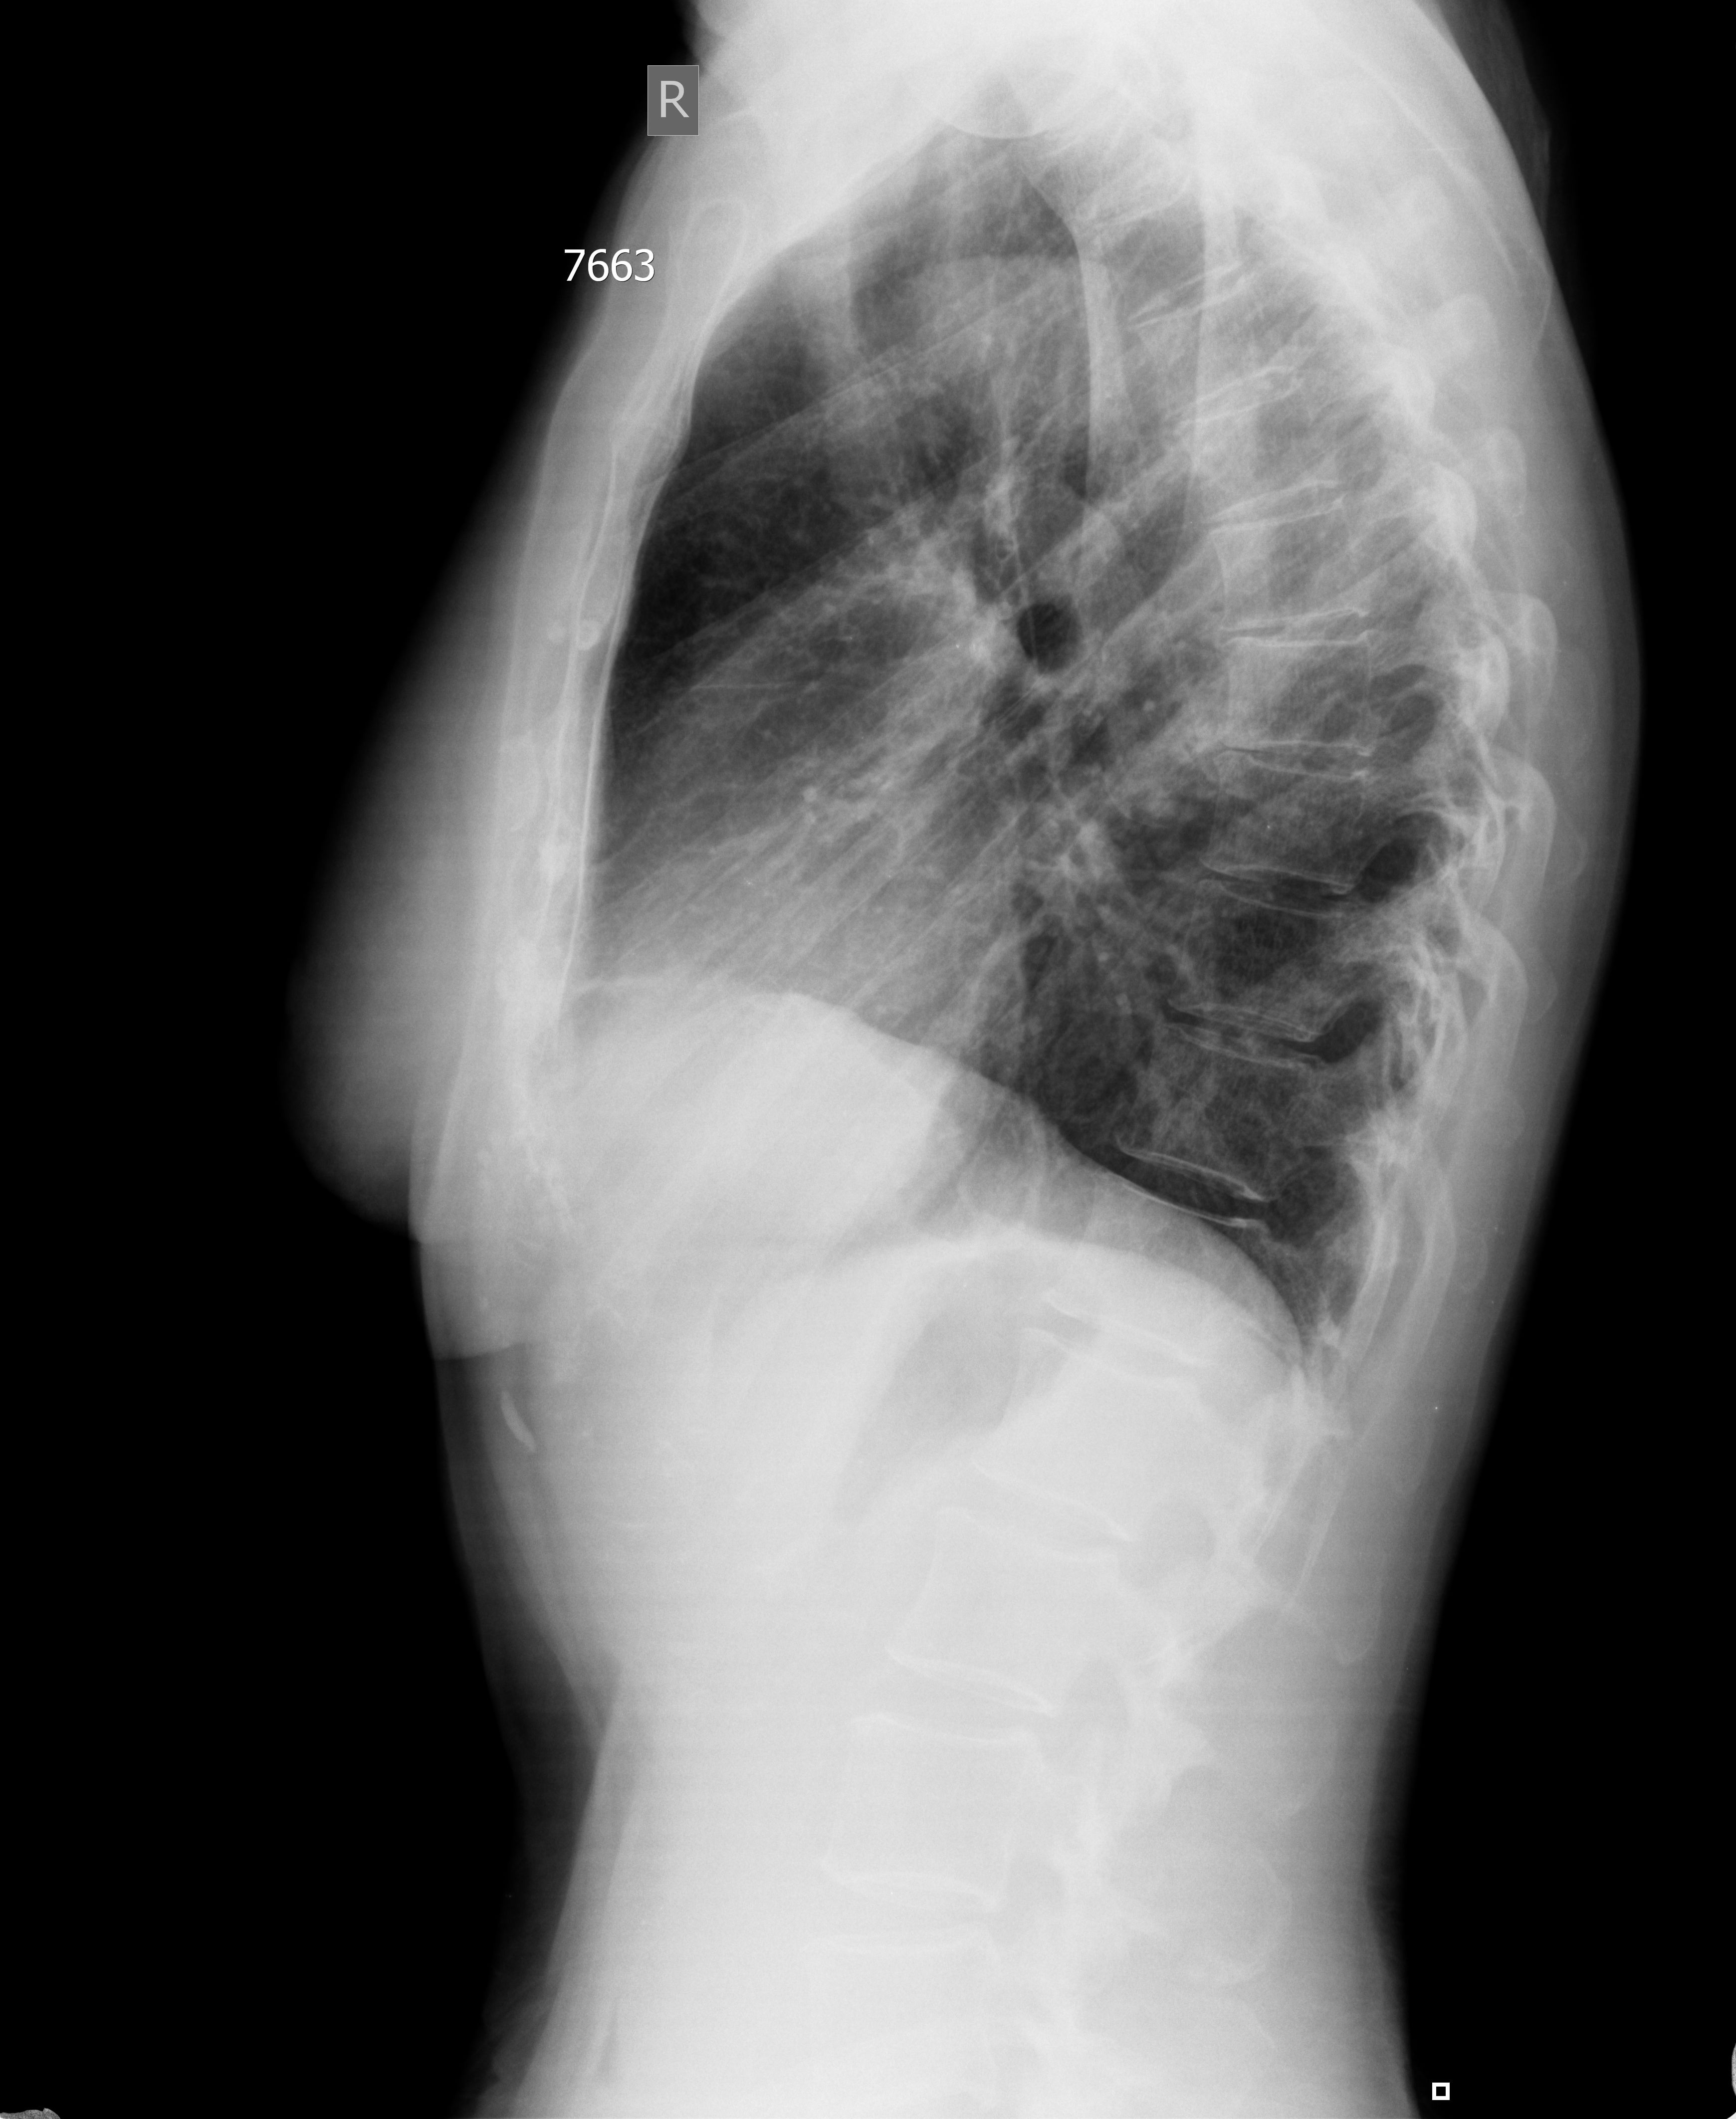

Женщина средних лет. Профилактическое УЗИ. Жалоб не предъявляет.

Ответ радиолога по РГ

Спайки vs Липома vs Другое в правом кардиодиафрагмальном синусе

ro -grama - Krūtinės ląstos organų 2-jų krypčių rentgenogramos Pleuros sinusai laisvi. Dešinėje kardiodiafragminis sinusas seklus - sąaugos ar lipoma ar kita? Dešinėje deformuota diafragma dėl dalinės relaksacijos? Plaučių piešinys pagausėjęs deformuotas. Šaknys struktūrinės. Širdis - n.y. Ao - suintensyvėjusi.